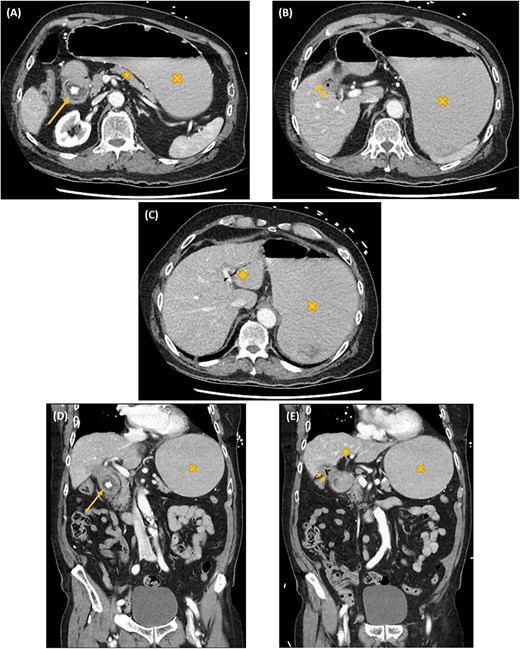

Axial (A–C) and coronal (D, E) computed tomography images showing gastric outlet obstruction (cross) due to a 3 cm hyperdense ectopic gallstone between the first and second parts of duodenum (arrow), with intrahepatic pneumobilia (diamond) and a decompressed gallbladder (arrow heads). This Rigler’s triad of findings was consistent with a cholecystoduodenal fistula and Bouveret syndrome.

On investigation, an acute inflammatory response, an acute kidney injury and a marked metabolic alkalosis were evident on biochemistry, but there was no cholestasis or hepatic dysfunction. Subsequent abdominal computed tomography (CT) identified a 3 cm hyperdense ectopic gallstone that was impacted between the first and second parts of the duodenum. There was gastric outlet obstruction proximal to this gallstone. A cholecystoduodenal fistula was noted with the presence of intrahepatic pneumobilia. These findings are collectively known as the Rigler’s triad (Fig. 1). Following initial resuscitative measures, an emergency laparotomy was undertaken. The operation was 3 h in duration and consisted of extensive adhesiolysis, duodenorrhaphy following stone extraction, subtotal cholecystectomy and finally an omental patch of the cholecystoduodenal fistula. On post-operative Day 6, his recovery was complicated with bilateral pulmonary emboli leading to both respiratory failure and obstructive shock. Despite thrombolysis and resuscitation, he succumbed 10 h later.